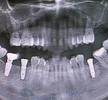

علاج الزرعات السنية

التهاب ما حول الزرعة السنية (Periimplantitis)

التهاب مخاطية الزرعات (Peri-Implant Mucositis)